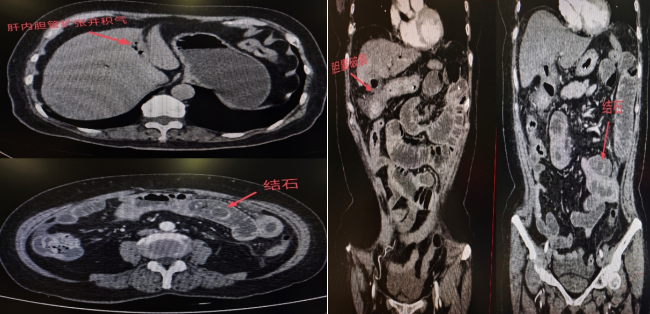

腹部CT检查结果显示:李阿姨的胆囊已经发生穿孔,一枚结石从破口处掉进小肠,并牢牢卡在肠腔内,形成了机械性肠梗阻。由于结石嵌顿时间较长,导致局部肠壁明显水肿和炎症。